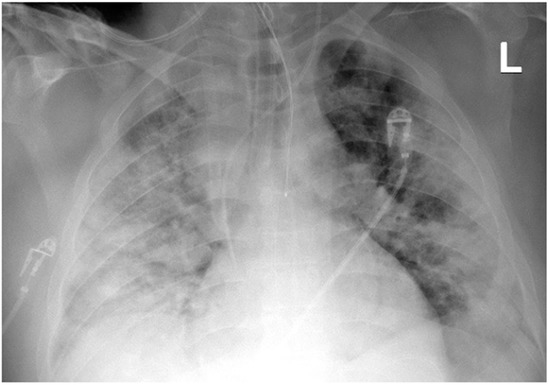

A 41-year-old obese man with a BMI of 44.5 kg/m2 (class III obesity) was admitted to the ICU on day 2 after admission to the hospital due to respiratory failure in the course of SARS-CoV-2 infection. The patient had comorbidities: type 2 diabetes mellitus and obstructive sleep apnea. On admission to the hospital, a CT scan of the lungs showed lesions typical of COVID-19 (Figure 3).

Figure 3. ICU: (A) upper lung segments; (B) middle lung segments; (C) basal lung segments (Case 2).